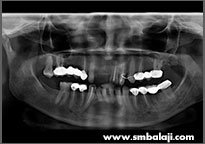

X-ray showing 6 impacted teeth- upper right and left third molars and lower right and left third and second molars